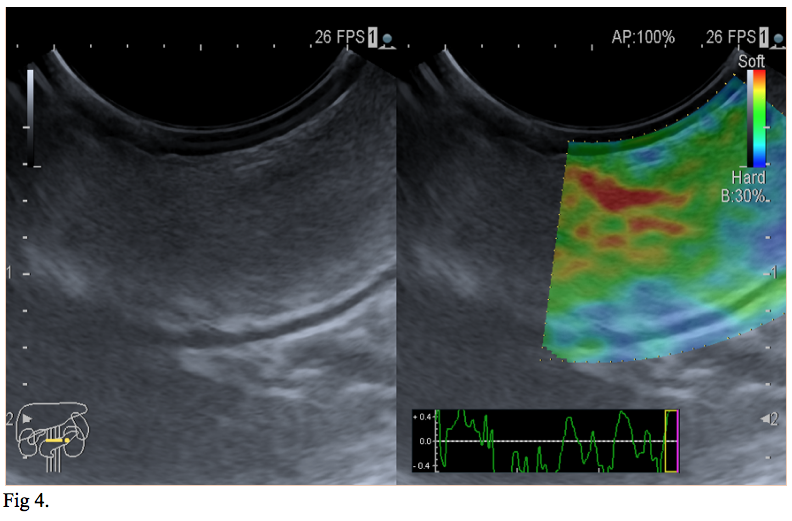

We report the case of a 66-year-old gentleman, known to suffer from high blood pressure, diabetes mellitus type 2, dyslipidemia, cervical and lumbar spondylosis, who presented to the emergency department with asthenia, pallor, melena. On physical examination, the patient was tachycardic with a heart rate of 120, and had a blood pressure of 100/60. He was pale but conscious and orientated. Cardiovascular and respiratory examinations were normal. His abdomen was soft, non-distended, bowel sounds were present and no palpable masses were felt. His laboratory investigations showed a mild normochromic, normocytic anaemia, low haematocrit, hyperglycemia, hypercholesterolemia. The patient was initially resuscitated and stabilized with intravenous fluids and proton pump inhibitors were initiated (iv 80 mg bolus and continuous infusion 8 mg/h). A naso-gastric tube was inserted which produced 300 ml of fresh blood. The patient underwent an urgent upper GI endoscopy which revealed an antral submucosal tumour with an ulcer over the mass. No active bleeding was seen during the procedure. A CT scan of the abdomen and pelvis highlighted a 30/20/18 mm oval shaped soft tissue lesion of fat density arising from the posterior wall of the stomach, with no associated lymphadenopathy. The liver, spleen, and pancreas all appeared normal (Fig 1,2). EUS has been performed and revealed a 30/18 mm intensely hyperechoic lesion continuous with the submucosal layer of the GI tract wall. The lesion was also soft on elastography, and as all the features were suggestive of a benign lesion, tissue sampling was not performed at that stage (Fig 3,4). The patient’s case was discussed at the Tumor Board meeting. The joint decision was to proceed with an exploratory laparoscopy and resect the benign mass. Histopathological examination confirmed the diagnosis of lipoma (Fig 5,6).

Regarding our case, based on the endoscopic appearance and location of the SELs, gastrointestinal stromal tumor (GIST), a neoplastic lesion with malignant potential was the most likely diagnosis. Differential diagnosis included surely benign lesions such as a lipoma, leiomyoma or schwannoma. The diagnosis of lipoma was suspected on abdominal CT scan and was confirmed by EUS. The joint decision to proceed with an exploratory laparoscopy and resect the benign mass was made based on the latest recommendation of the American Society for Gastrointestinal Endoscopy (ASGE). The suggestion of ASGE was that symptomatic GI lipoma should be resected or followed up.